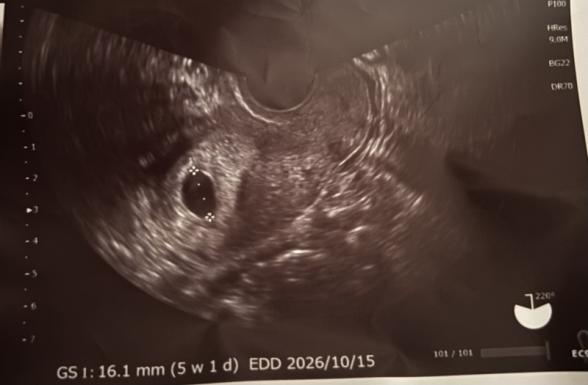

こんにちは。2回目の超音波検査で心拍確認ができませんでした。最終月経開始日は去年の12月17日頃で、今頃7週〜8週目くらいだと思います。前回の検査で袋と言われる物が4.6mm。排卵が遅れてるかも?と言われてました。2週間後の2回目で16.1mmになっていました。しかし、心拍確認は確認できず、医者には確認できて欲しいけどねーと言われました。その後のお話で1週間後に来てくださいと言われました。もし確認できなかったら流産の可能性があると言われました。生理二日目ぐらいの出血などがあることも説明されましたが、今のところ茶おりが小指の爪程度で出る頻度も少なく、お腹が痛いことも少ないです。元々生理周期がちゃんとしてる訳でもなく、数日〜1週間ズレることも多々ありました。ただ遅れているだけだと願いたいです。

1回目の検査で5週目くらいと言われ、2回目の今回は何も言われませんでした。しかし写真には5週目と記載されていて何が何だか分かりません。元々タバコも吸っており辞めるために我慢などしてストレスを感じてしまっていたのでしょうか。又、タバコのせいもあるのでしょうか。流産と言う言葉を聞きとても悲しくなりまたタバコを吸ってしまいました。

胎嚢の大きさから週数を割り出すと5週と出てきていたのだと思います。